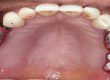

Systemic lupus erythematosus (SLE) presents as a chronic inflammatory autoimmune disease that can often demonstrate multisystem involvement. Since, immune-suppressive drugs are used in the treatment of this disease, it can possess an elevated risk of infection and delay healing. Moreover, damage to the salivary glands in this disease leads to reduced salivation. Together, these complications can be a primary concern in dental treatment procedures owing to inability to maintain oral hygiene and risk of implant failure. This is the first case report in literature to our knowledge and it represents a treatment option and procedure for immediate full mouth rehabilitation after extraction without raising flaps using basal cortical screw implant in a patient who was on corticosteroid for over 20 years as she was diagnosed with Systemic Lupus Erythematosus. Since there are very few cases of SLE reported in literature with the use of oral implants, treating these patients can often pose a challenge.